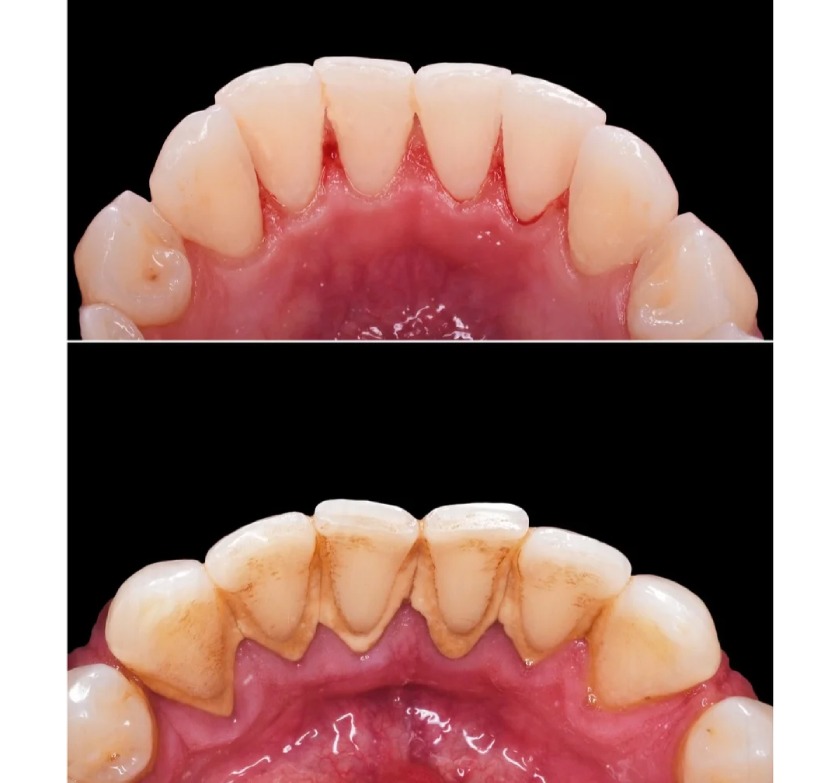

Mặc dù bạn có vệ sinh răng miệng đúng cách hàng ngày, vẫn có thể có mảng bám và vi khuẩn tích tụ lâu ngày trên bề mặt răng cũng như bên dưới nướu. Cạo vôi răng giúp loại bỏ những mảng cứng đầu này, giúp răng sáng bóng và chắc khỏe hơn.

Cạo vôi răng giúp loại bỏ mảng bám, vi khuẩn trên răng hiệu quả